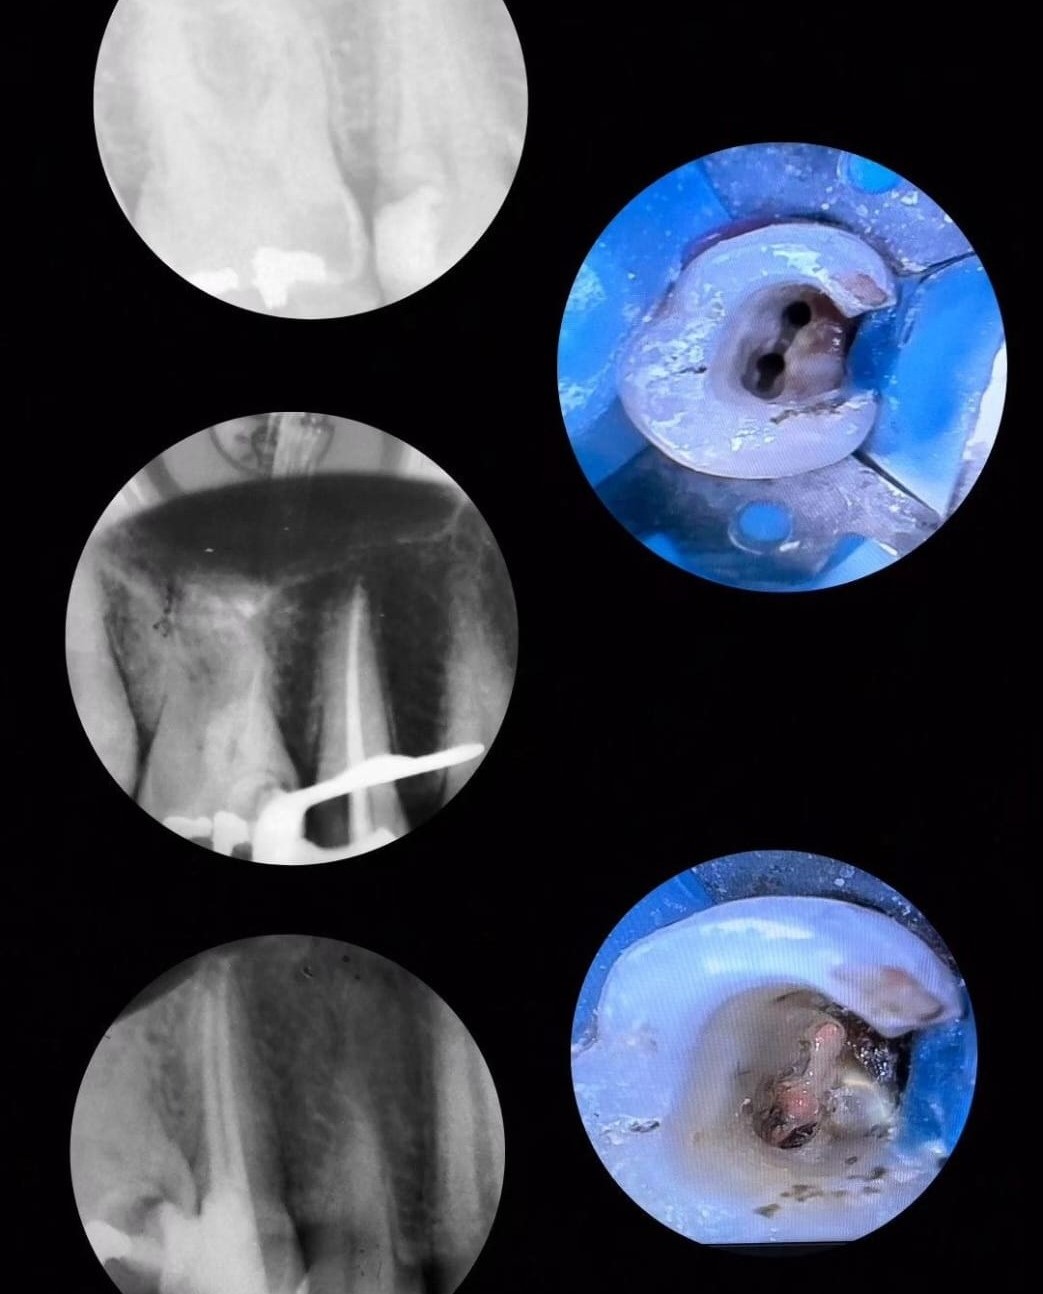

Post 1

Post 2

Post 3

Post 4

Post 5

Post 6